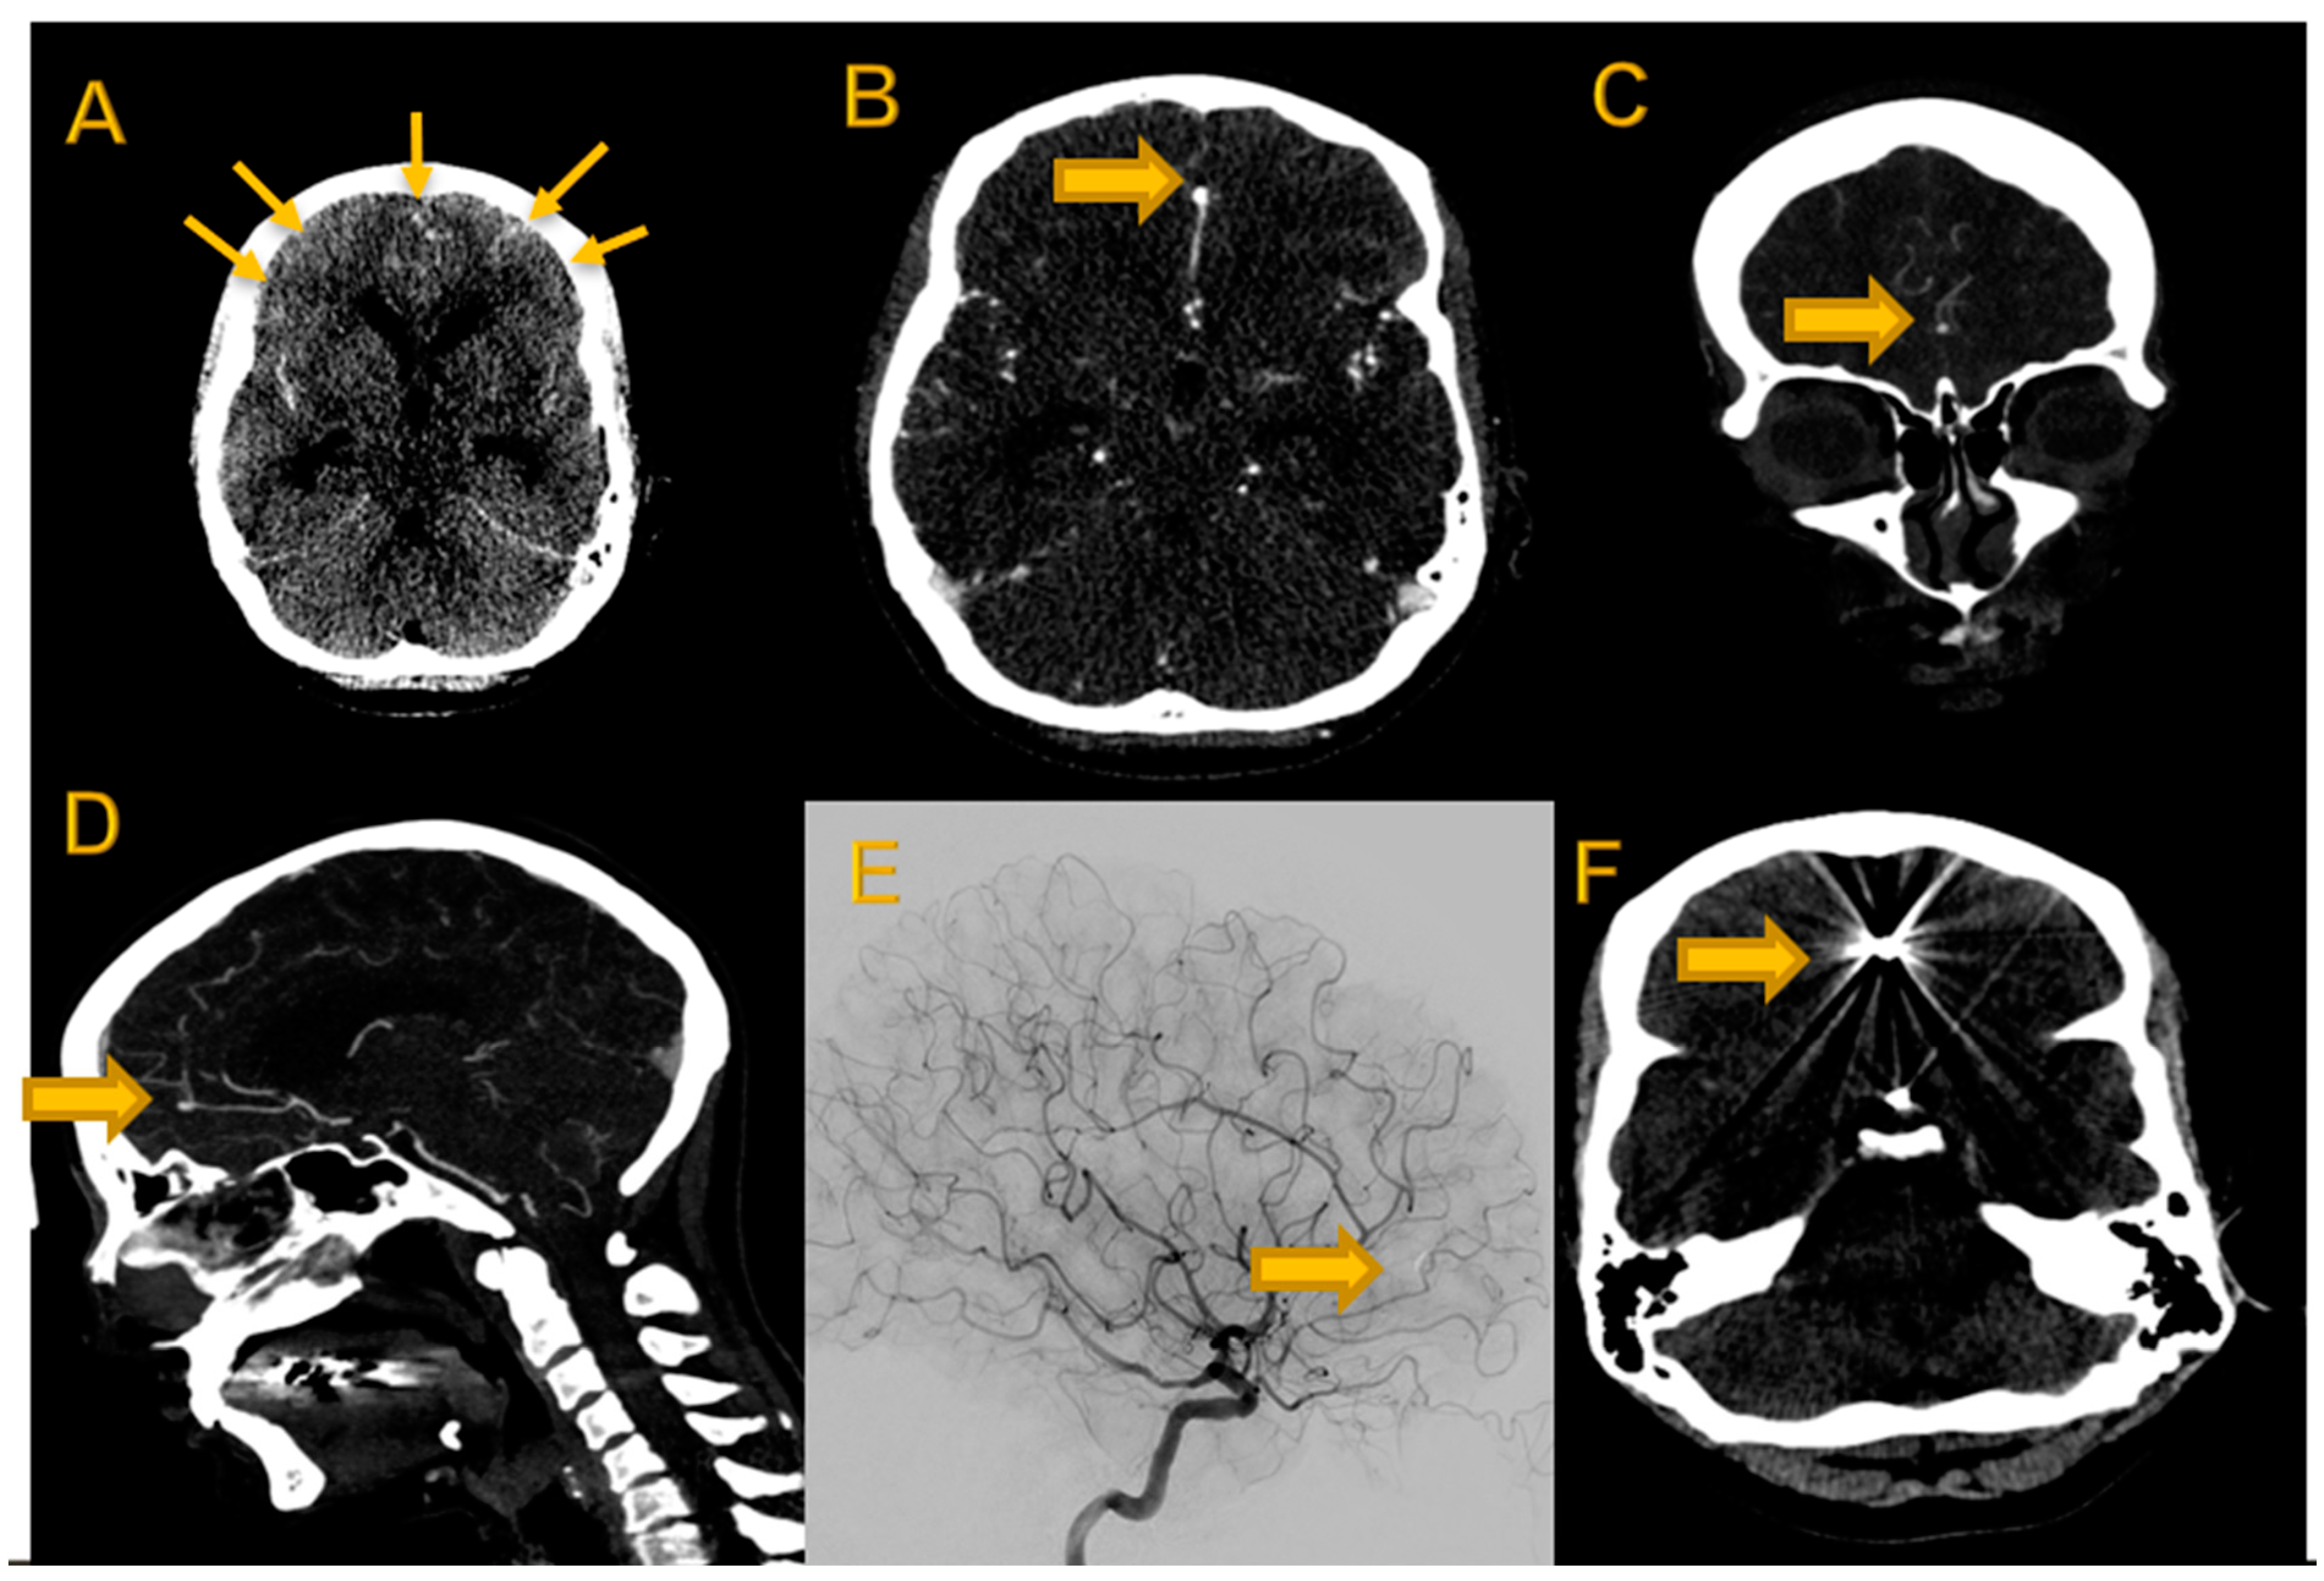

Figure 1.

Imaging dataset of 42-year-old female patient with acute intracranial hemorrhage due to ACA aneurysm. (A) Non-contrast-enhanced axial cCT showing SAH [arrows]. (B) Contrast-enhanced axial slice with ACA aneurysm [block arrow]; (C) coronal reconstruction MIP with ACA aneurysm (block arrow); (D) sagittal reconstruction MIP with ACA aneurysm (block arrow) and (E) DSA after clipping (block arrow). (F) Postinterventional non-enhanced cCT with clip (block arrow).

This study was conducted retrospectively in a single center between September and December 2021. The study protocol conforms to the ethical guidelines of the 1975 Declaration of Helsinki. Patients who presented to the emergency department with suspected bleeding between June 2016 and January 2018 were retrospectively screened. Cases with a history of intracranial surgery were excluded and the first 30 cases with aneurysm detection and the first 30 cases with aneurysm exclusion based on initial clinical reports and confirmation by the head of the neuroradiology department with more than 25 years of experience in clinical CT reading were included in our retrospective analysis. The reference reading was performed using all possible (routinely generated) reconstructions on a medical-grade monitor workstation and patients’ medical history up to the time of their cranial CT scan (Figure 1).